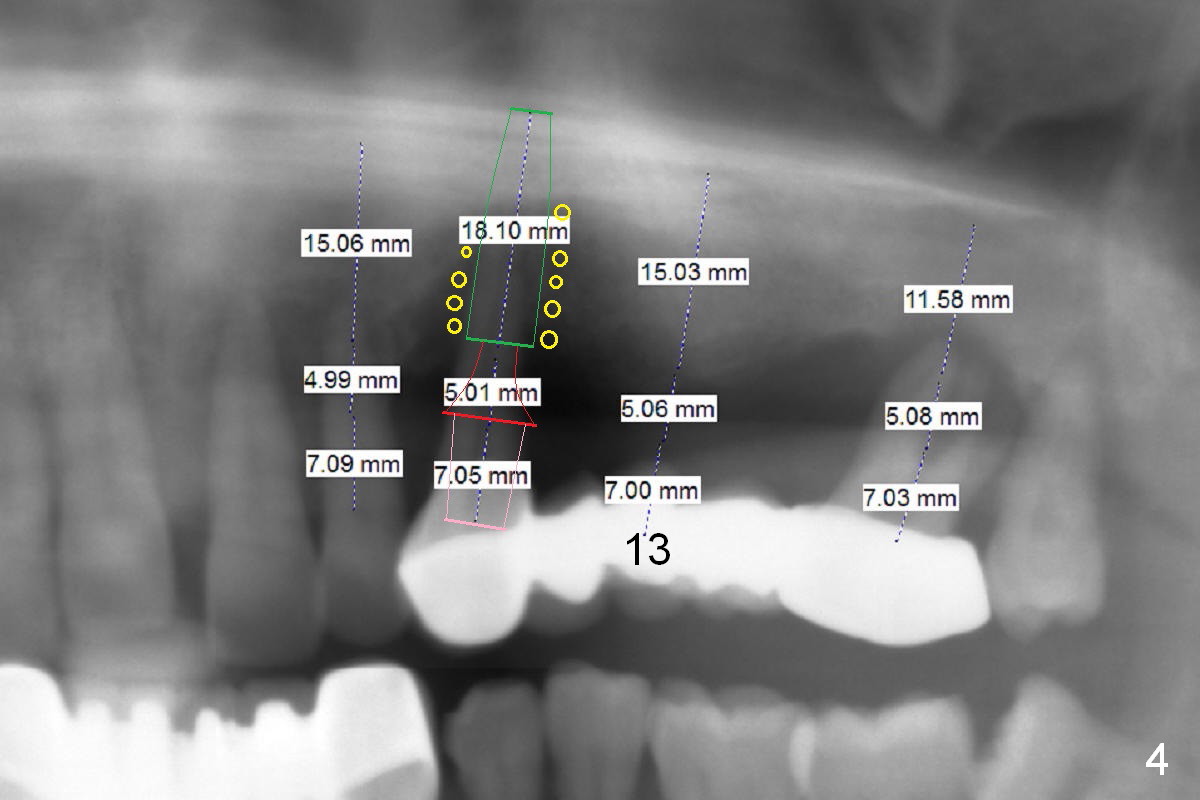

A 45-year-old man has advanced periodontitis and bruxism (sufficient remaining bone height, Fig.1).  Full mouth restoration will be done by quadrant with preservation of a few of relatively healthy teeth.  The 1st quadrant to be treated will be the upper left (Fig.2).  The teeth #9-11 and 15 will be extracted (Metronidazole) with immediate implants.  A delayed implant will be added at #13 for #11-15 bridge (Fig.4).  In addition to the large radiolucency around the roots of #9 and 10 (Fig.3 red dashed line), the gingiva at #11 and 15 is excessively thick (red arrows).  For example at #11, a long implant has to be placed a little more outside the bone (Fig.4 green area), since the longest cuff of the abutment (red area) is 5 mm for UF implant system.  The longer the cuff, the less amount of the implant will be outside the bone with less chance of periimplantitis.  When the coronal implant threads are exposed, a large amount of bone graft has to be placed (Fig.4 yellow circles).